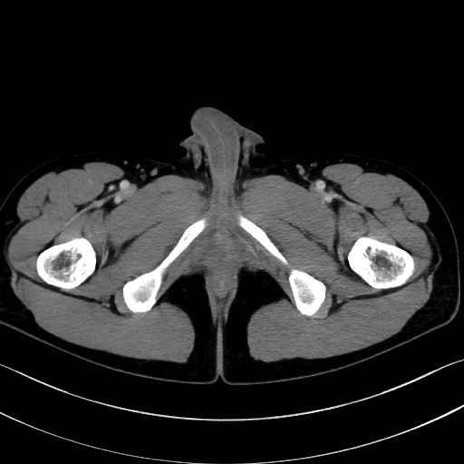

梨状筋(piriformis muscle) のCT画像の解剖

梨状筋 (Piriformis)

内閉鎖筋 (Obturator internus)